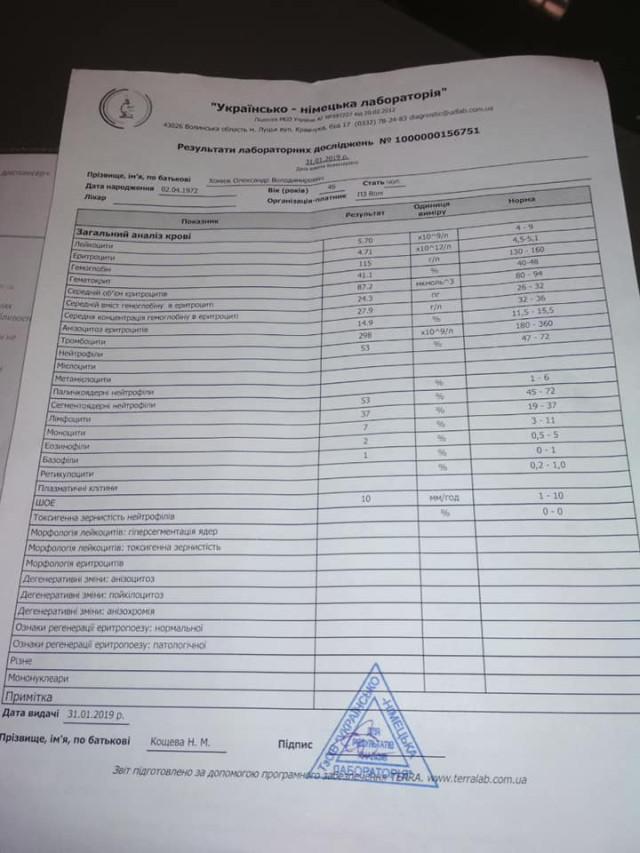

Волинянин Олександр Хомюк потребує допомоги у боротьбі з раком.

Як повідомили його близькі у Фейсбуці, у нього негоджкінська лімфома великих клітин В, початок 4 стадії.

Як повідомили його близькі у Фейсбуці, у нього негоджкінська лімфома великих клітин В, початок 4 стадії.